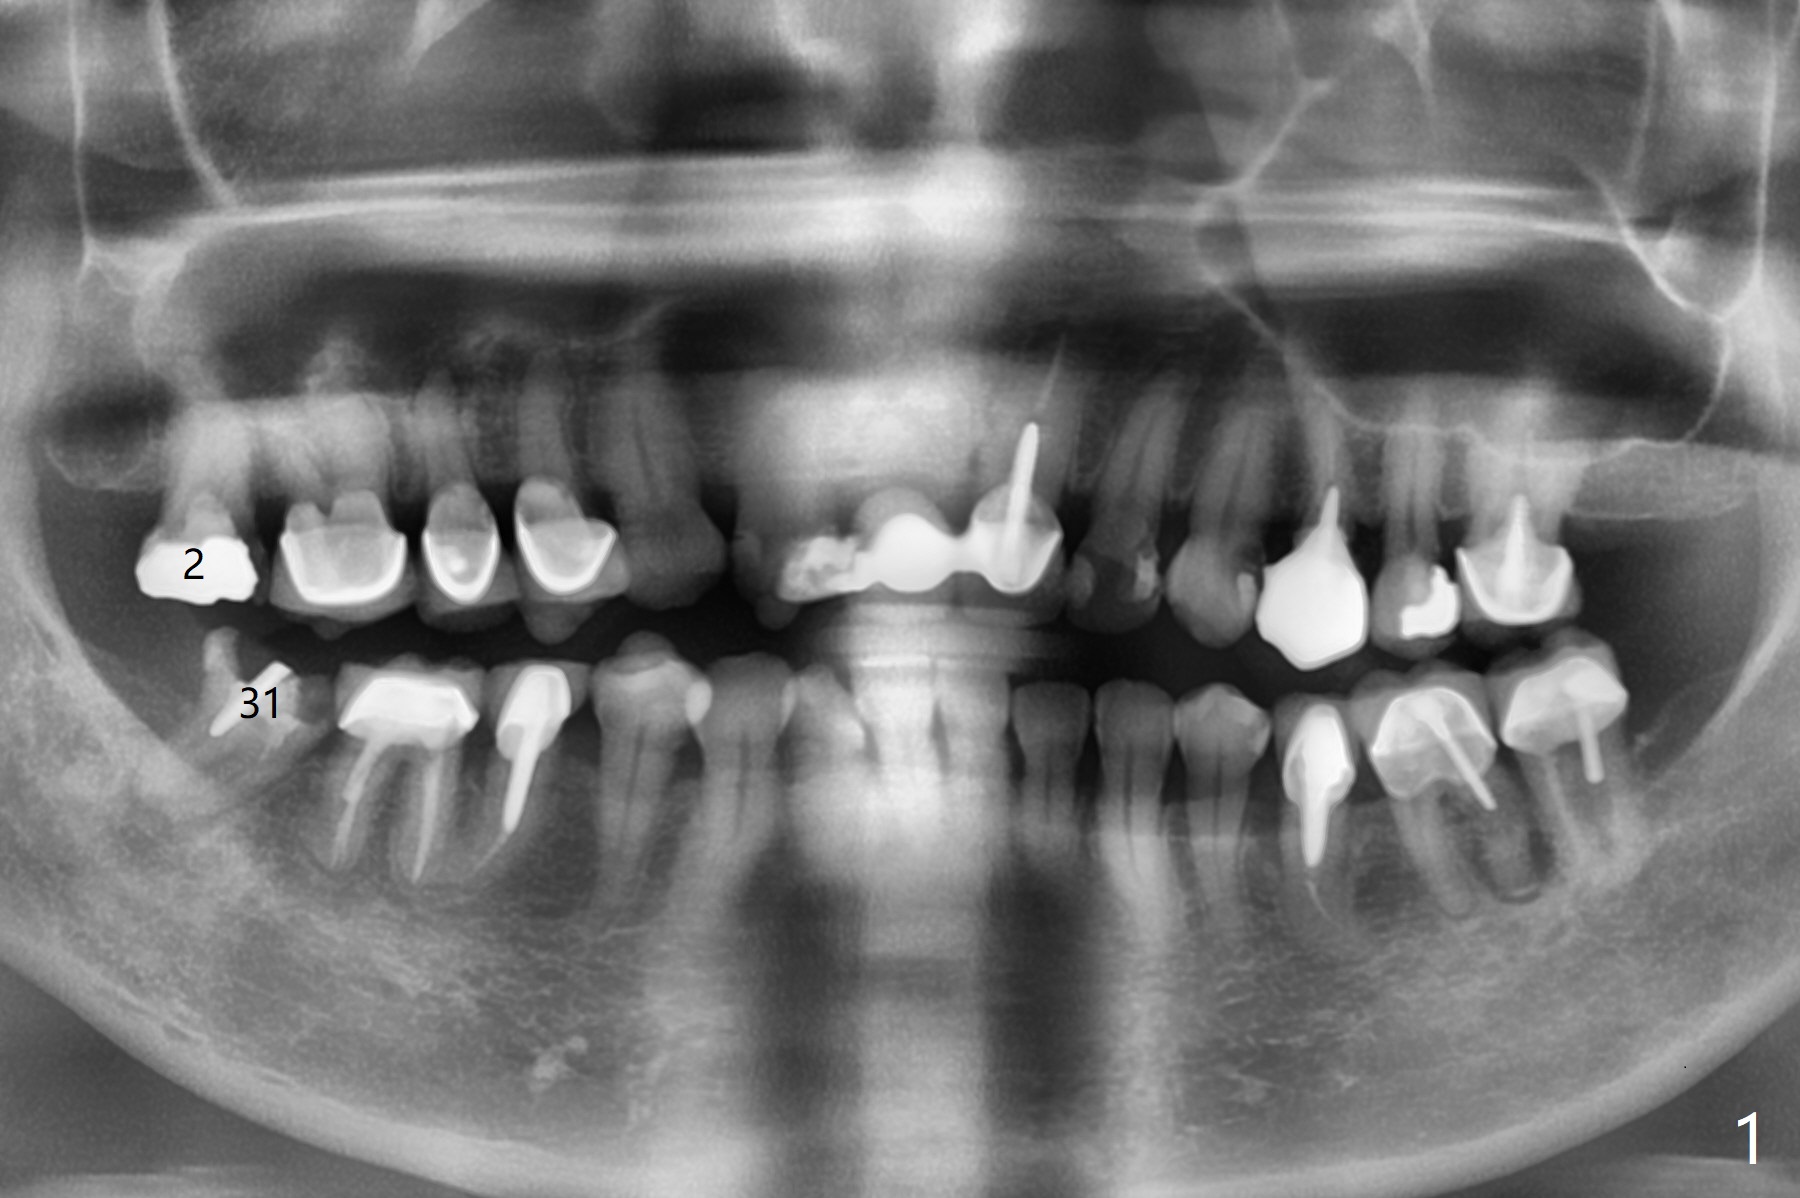

Immediate Upper and Lower 2nd Molars

A 62-year-old woman requests implants at #2 and 31. PRFx2

31 Surgery

2

31

下齿槽神经